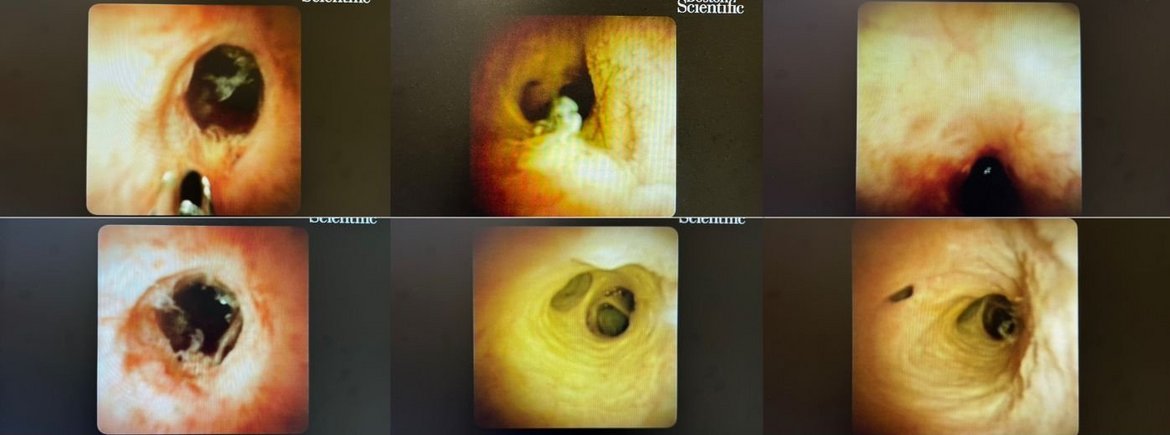

Bilder aus dem Gallengang und der Gallenwegen in der Leber. Unterschiedliche Bilder mit entzündlichen oder tumorösen Verengungen, sowie Normalbefunde (Quelle: Boston Scientific)

Bei der Diagnostik der Gallengänge bietet die Cholangioskopie eine Reihe von Vorteilen gegenüber der konventionellen Cholangiographie, die nur eine indirekte Röntgendarstellung ermöglicht. Die Cholangioskopie entspricht der direkten Endoskopie der Gallenwege und erlaubt eine direkte Beurteilung von biliären Strukturen, sowie die gezielte Entnahme von Gewebeproben und die effektive Behandlung von Gallensteinen. Hierzu stehen verschiedene Techniken wie die intraduktale elektrohydraulische Lithotrypsie (EHL) oder die intraduktale Laserlithotrypsie (ILL) zur Verfügung.

Die Cholangioskopie kann immer dann angewendet werden, wenn eine detaillierte Untersuchung und Therapie der Gallenwege erforderlich sind und bietet den direkten nicht operativen Zugang zu den Gallenwegen und die Möglichkeit der breiten Interventionen ohne belastende Operation.

Die Cholangioskopie kann als direkte oder indirekte Cholangioskopie durchgeführt werden: Bei der direkten Cholangioskopie werden dünne obere Endoskope peroral eingeführt und direkt zur Penetration der Papilla duodeni major genutzt. Bei der indirekten Cholangioskopie werden sogenannte Mother-Baby-Systeme eingesetzt. Hier wird ein ultradünnes Endoskop durch den Instrumentierkanal eines Duodenoskops, wie es zur ERCP genutzt wird, transpapillär eingeführt. „In den Sana Kliniken Düsseldorf findet die indirekte Cholangioskopie mit dem SpyGlass System von Boston Scientific breite klinische Verwendung und wird regelhaft zur Zertrümmerung von Konkrementen mittels elektrohydraulischer Lithotrypsie (EHL) und zur Palliation bei Malignomen eingesetzt“, sagt Chefarzt Dr. Birkenfeld.